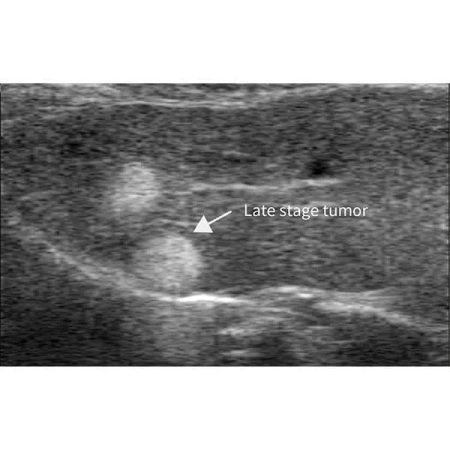

Помимо исследований сердечно-сосудистой системы, RevoSilex также широко используется в онкологии и разработке лекарств, где он помогает визуализировать кровоток в опухоли и оценивать терапевтическую эффективность. RevoSilex F30/F60 обеспечивает высококачественную визуализацию в режиме реального времени для ускорения научных исследований в области болезней и генетики.